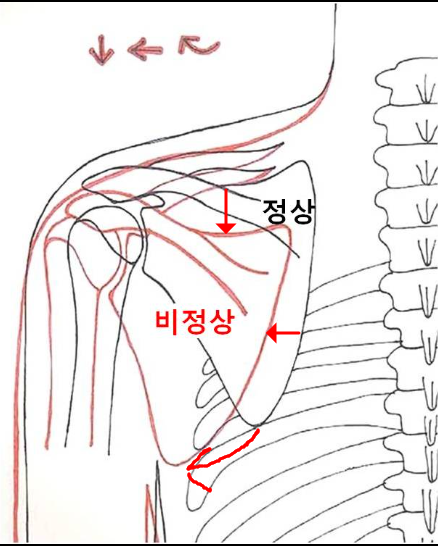

견갑골 운동장애의 기전

"견갑골의 과도한 전인상태, 견봉올림어려움 등이 충돌 유발"

앞서 말했던 원인들에 의해서 겹갑골은 과도한 견갑골의 앞으로 빠진상태인 전인상태(견갑골 벌어짐, Protraction, 후인이 잘 안됨)와 견봉 올림(Acromial elevation)이 어려움에 의해서 충돌이 더욱 쉽게 일아날 수 있습니다.

굽은등, 거북목 -> 견갑골 전인상태 -> 견봉하공간 좁아짐 -> 충돌 증가

소흉근, 이두근 단두의 단축 -> 앞쪽기울임(Anterior tilting) 상태가 유지 -> 충돌 증가

그 외 견갑골 주변 근육 문제 -> 견갑골 운동장애

과도한 어깨 앞으로 빠짐상태인 전인 상태가 유지되고, 후인은 잘 되지않게되면 견관절의 관절와(Glenoid)에 해부학적문제가 아닌 기능적인 앞쪽기울어짐(fuctional anteversion)이 발생되면서 관절와순(Glenoid labrum)에 상완골두가 잘 밀착되지 않고 붕 뜨게 되면서 앞쪽 어깨의 안정성이 떨어지면서 손상에 취약하게 됩니다. 이는 결국 어깨 전방 탈구(Anterior dislocation, 어깨 탈구의 95% 차지, https://www.youtube.com/watch?v=xDePRKeB4kc)가 더 쉽게 발생할 수 있게됩니다.

참고로 어깨 앞쪽 전방탈구는 외전, 신전, 외회전 시 발생되며 위와같이 관절와의 기능적인 앞쪽 기울어짐상태 시 더 잘 발생할 수 있습니다.

반면 어깨 뒤쪽은 상대적으로 관절와와 상완골두가 좁아지며 외회전, 수평외전 시 극상근, 극하근이 관절와순과 충돌이 많아지며 내적충돌을 일으킬 수 있습니다.(Internal impingement) 이 때 내적충돌은 전상방, 후상방에서 각각 일어날 수 있고, 주로 후상방에서 나타납니다.

참고로 내적충돌증후군은 어깨후방의 관절낭의 구축에 의해서 발생되며, 야구에서 투수가 공을 반복적으로 던지면서 생길 수 있습니다.